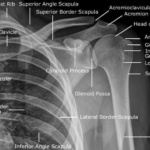

Las radiografías, generalmente llamadas rayos X, producen imágenes como sombras de huesos y ciertos órganos y tejidos. Las radiografías son muy buenas para detectar problemas óseos. Pueden mostrar algunos órganos y tejidos blandos; sin embargo, la MRI y la CT suelen crear mejores imágenes de los mismos. Aun así, las radiografías son rápidas, fáciles de obtener y menos costosas que los otros estudios, por lo que se pueden usar para obtener información rápidamente.

Un tubo especial dentro de la máquina de rayos X emite un haz de radiación controlada. Los tejidos del cuerpo absorben o bloquean la radiación en diferentes grados. Los tejidos densos como los huesos bloquean la mayor parte de la radiación, pero los tejidos blandos, como la grasa o los músculos, bloquean menos radiación. Después de pasar por el cuerpo, el haz alcanza una pieza de un fragmento de película o un detector especial. Los tejidos que bloquean altas cantidades de radiación, como los huesos, aparecen como áreas blancas en un fondo negro. Los tejidos blandos bloquean menos radiación y aparecen en tonos de gris. Los órganos que contienen principalmente aire (como los pulmones) aparecen en negro. Los tumores son por lo general más densos que el tejido que los rodea, por lo que suelen verse en tonos grises más claros.